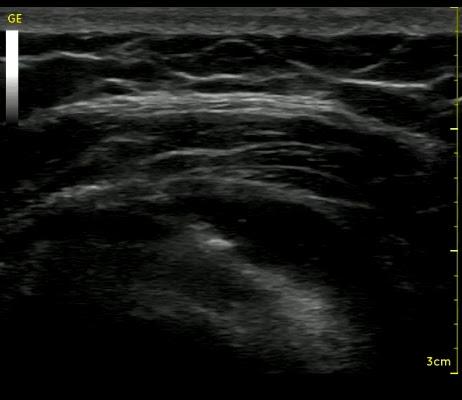

Στο ιατρείο διενεργείται υπέρηχος του μυοσκελετικού συστήματος - διαγνωστικά σε αρθρώσεις και περιαρθρικούς ιστούς, και θεραπευτικά κατευθυνόμενες παρακεντήσεις.